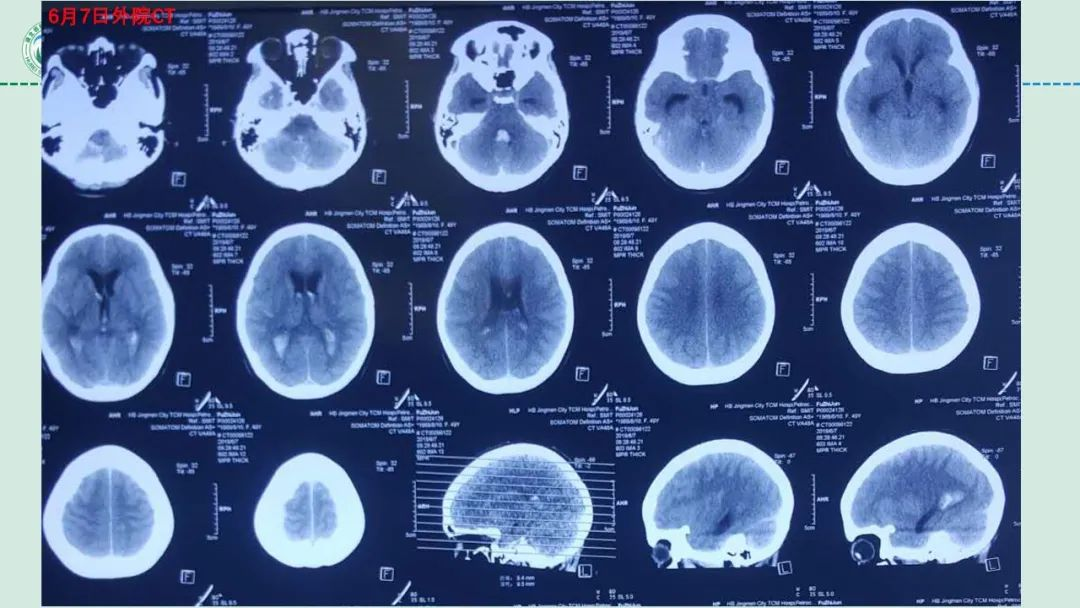

李俊教授团队:右侧PICA延髓扁桃体段多发动脉瘤

今日与大家分享的是《正海-妙术视界》第二百三十二期,由湖北省第三人民医院李俊教授团队带来的右侧PICA延髓扁桃体段多发动脉瘤,欢迎观看、分享。